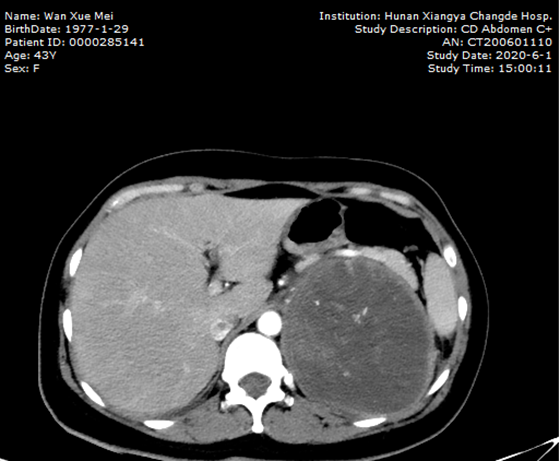

43岁的万女士因左侧腰腹痛1年,加重伴发热,慕名来到湘雅常德医院泌尿外科就诊。万女士曾经有过两次剖宫产经历,入院后完善相关辅助检查后显示:左侧肾上腺区有一个巨型肿瘤。那么,这也就意味着左侧肾上腺恶性病变的可能性极大,且极有可能导致皮质癌。术前经过科室讨论及与患者充分沟通后,泌尿外科团队决定为其实施“经腹入路腹腔镜下左侧腹膜后巨大病损切除术”。

术前

手术在泌尿外科主任顿金庚教授的指导下,由蒋欣杰教授肿瘤组团队进行手术。术中腹腔镜下见左侧肾上腺巨大肿块,肿块直径长达14厘米,表面血管丰富,与胰腺、脾脏、左侧肾蒂血管非常密切,其难点在于肾静脉和肾动脉及胰腺之间的处理,且患者术中血压波动较大。最高血压达230/130mmHg,最低低血压达68/34mmHg,心率最高达199次/分,以触碰瘤体为甚,经过复杂而繁琐的腹腔镜下的游离操作后,终于顺利切除巨大肿瘤,术毕经pacu苏醒返回病房。目前,患者术后各项身体机能恢复良好。

左侧肾上腺巨大肿块直径长达14厘米